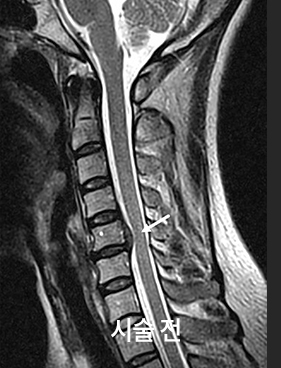

목디스크(경추 추간판 탈출증)는 목뼈 사이 디스크가 돌출되면서 신경을 자극해,

목·어깨·팔로 이어지는 통증이나 저림이 나타날 수 있습니다.

증상과 검사 결과에 따라 약물·물리치료·주사치료 등으로 통증 조절을 돕고,

필요한 경우 다음 단계 치료 옵션을 함께 안내합니다.

목과 팔의 통증을 유발하는, 튀어나온 경추 디스크(목 디스크)를

치료하기 위한 최소 침습 시술입니다. 약물 치료나 물리 치료 같은 보존적 치료에

반응이 없는 환자들에게 고려될 수 있습니다.